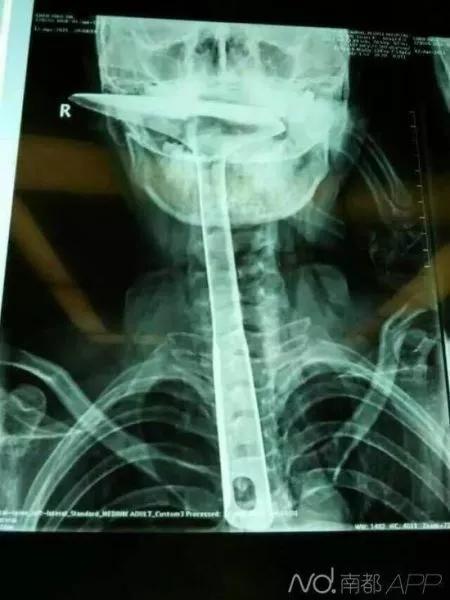

但是并没有将全部实情告诉医生,随后通过X光片检查后,医生们都震惊了!!!!

X光片显示男子的直肠里,竟有一个瓶状物!

最终医生为大叔进行了“直肠异物取出术”,这就是藏在体内的瓶子,长18cm、直径5cm的花露水瓶!

2015年5月,东莞虎门陈师奶,因喉咙难受将30公分的炒菜锅铲插进食道,结果导致食道表皮粘膜损伤严重,且被捅破了一个洞!